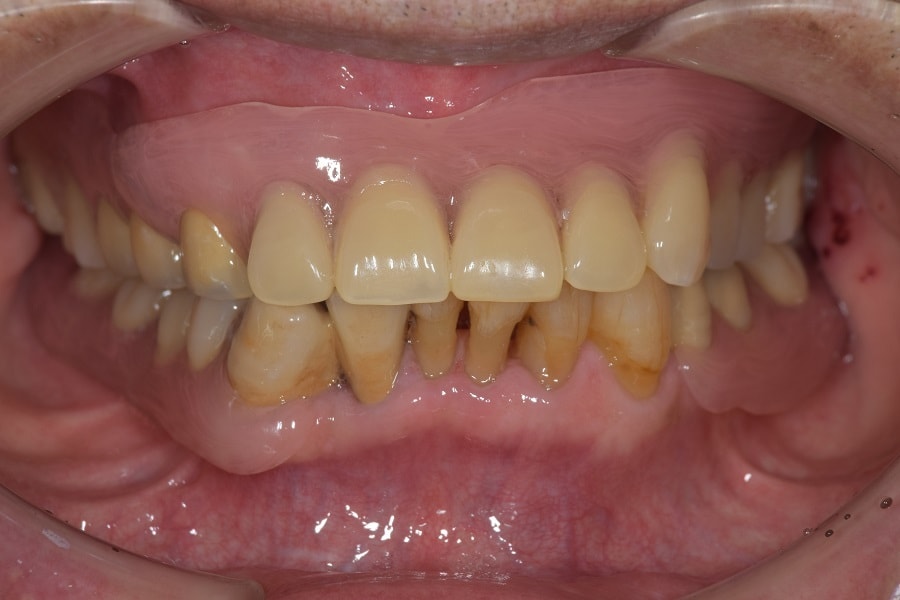

咬むと前歯が痛いと来院された患者さん。奥歯がないため、前歯に負担がかかり、下の歯がないまま放置していたため、上の歯が下に下がってしまうなど様々な問題をお口の中に抱えていました。

治療前のかみ合わせのままで治療しても長持ちしないこと、本来のかみ合わせから崩れてしまっていると判断し、お口の中を総合的に治療する治療方法を提案させていただき治療を行いました。

残すことが出来ない歯の抜歯などを行うと、すれ違い咬合という治療するには難しいかみ合わせであったことなど、仮の入れ歯などで咬合状態の経過観察などを行ったため治療期間は約2年ほどかかりました。